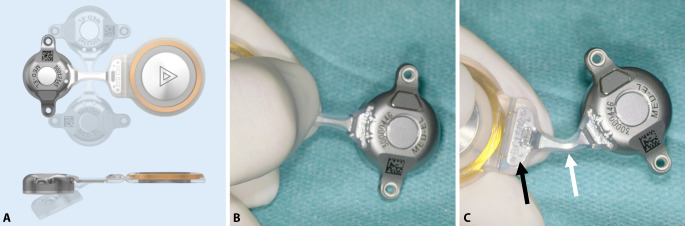

The implant can be bent in the transition zone, ±90° in the horizontal plane and −30° in the vertical plane (Fig. 5). While bending, the implant should be held with the thumbs and index fingers of both hands, one at the positioning aid and one at the BC-FMT (Figs. 1 and 5). The receiver coil and the attachment magnet are placed in a subperiosteal pocket, directly on the skull. The fixation wings with anchor holes should lay flat on the bone (Fig. 6A, B). When pressing the BC-FMT down with a finger, it should not wiggle or wobble. The BC-FMT is then fixed with self-drilling cortical screws (Fig. 6C, D).

Fig. 5.

Positioning the receiver coil and magnet. A The implant can be bent at the transition zone (white arrow in C) ±90° in the horizontal plane and −30° in the vertical plane. While bending, the implant should be held with the thumbs and index fingers of both hands; one hand should be placed at the positioning aid (B and black arrow in C), and the other hand should be placed at the bone conduction-floating mass transducer. (A: MED-EL, Innsbruck, Austria, with permission)

Fig. 6.

Fixing the bone conduction-floating mass transducer (BC-FMT) to the bone. A, B The fixation wings with anchor holes should lay flat on the bone. When pressing the BC-FMT down with a finger, it should not wiggle or wobble. C, D The BC-FMT is fixed with self-drilling cortical screws; this procedure is simpler in this model (BCI 602) than in the previous model (BCI 601). (A, C: MED-EL, Innsbruck, Austria, with permission)